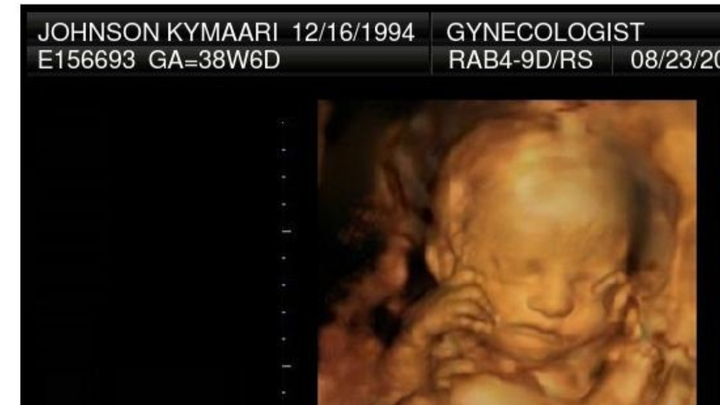

Hi im asking for help in getting my daughter cremated that i lost recently she was a still birth and we are trying to bring her home with us , anything would help